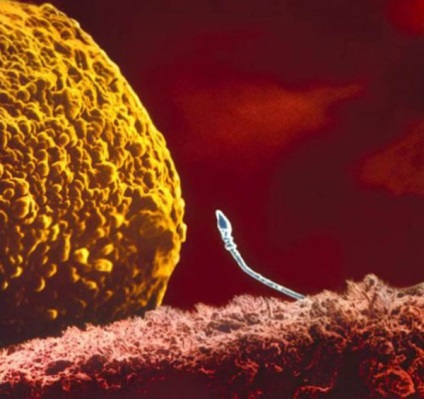

Sperma in trompa uterina se îndreaptă spre ovulului

Una dintre cele 200 de milioane de sperma paternă a pătruns prin coajă de ou

Sperma în secțiunea. Capul contine intregul material genetic.